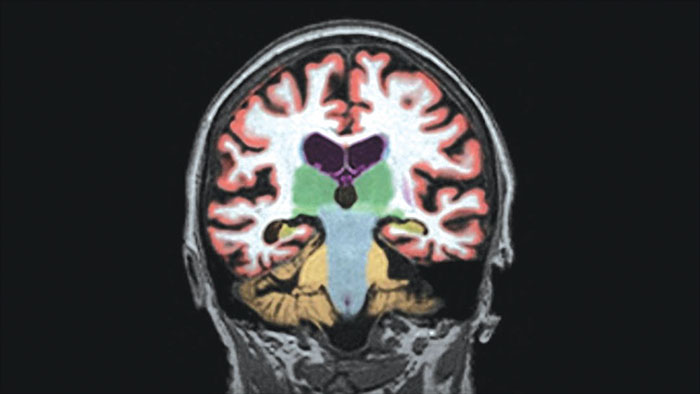

Automated brain image analysis solutions

MR NeuroQuant®* automatically segments and measures volumes of brain structures and compares these volumes to standard norms.

Benefits

* NeuroQuant is a trademark of CorTechs Labs, Inc.